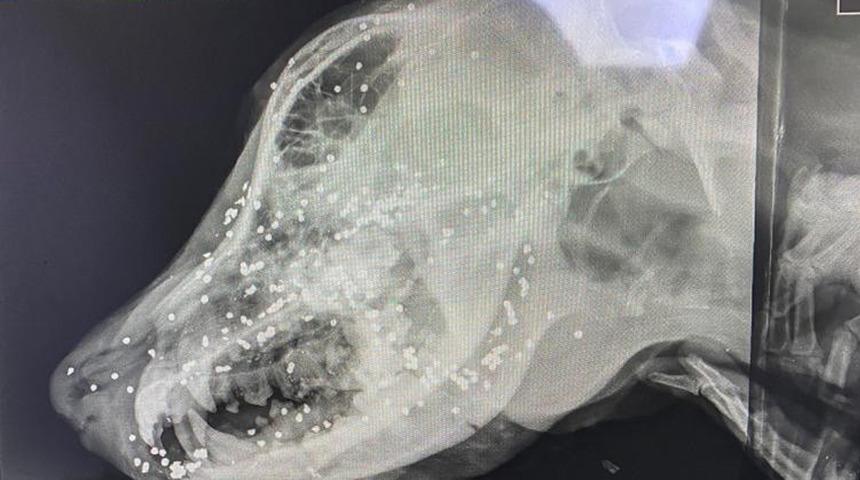

Köpek bakımevinde yapılan ilk müdahalenin ardından özel bir veteriner kliniğine gönderildi. Sol gözünü kaybeden köpeğin çekilen röntgeni ise vahşetin boyutunu ortaya koydu.

Köpeğin baş kısmında yaklaşık 90 adet saçma olduğu tespit edildi. Köpek veteriner de tedavi altına alındı. (İHA)